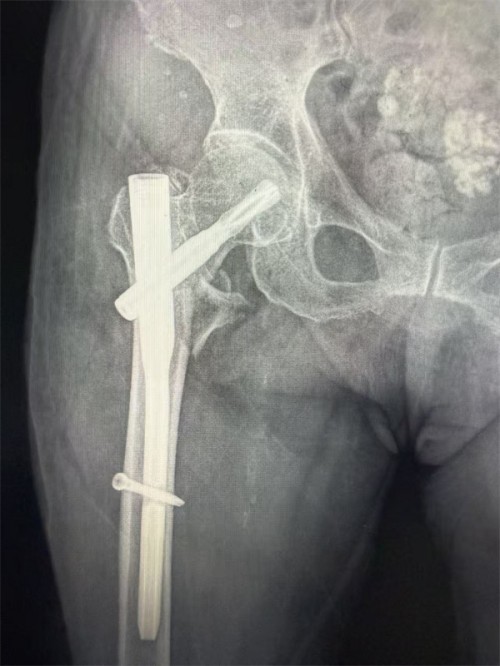

专家团队没有轻易放弃,温鑫柱选择微创髓内钉术式,该手术可以在1小时内完成,最大程度减少手术创伤及出血;姜丽考虑老人服用抗凝药物无法腰麻,且高龄患者尽量避免气管插管后,决定采用外周神经阻滞+镇静的麻醉方式,最大限度的减少麻醉药物对中枢系统的影响;王轩则对围手术期的心脏管理做了全面的指导及应急预案。同时,功能科、检验科、放射科等相关科室也积极配合应对,血库紧急备血,保证手术供血;放射科、功能科加急进行术前相关检查,为手术提供精准依据。不同于传统诊疗模式,团队不仅通过CT三维重建精准判断骨折类型,还对患者心肺功能、血压控制、营养状况等进行全面排查,在与患者家属进行全面的沟通后,最终制定了“闭合复位小切口髓内钉内固定术+精准麻醉+ERAS全程管理”的个性化方案,并决定于次日进行手术治疗。

手术当日,姜丽带领的麻醉团队摒弃传统全麻方案,采用“髂筋膜阻滞及股外侧皮神经阻滞+中度镇静”的精准麻醉方式,最大限度减少对老人心肺功能的影响。术中持续监测指标,确保生命体征稳定。B超引导(可视化)的神经阻滞,精准定位、精准给药,不仅使副作用减少,更能让镇痛的时间延长到术后。手术由温鑫柱和骨科李观清医生共同完成,仅用时40分钟便完成骨折复位与固定,术中出血不足50ml,创伤小、恢复快的优势尽显。